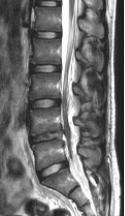

70岁的梁奶奶,家人说老人家因提重物导致腰背疼痛,正因疫情期间,在家休息仍无缓解,因疼痛无法正常生活,迫于为梁奶奶解除痛苦,居家7天后家人带其来到我院就诊,张昊主任医师阅读了相关影像学资料,经过团队的讨论,首先明确诊断为 “1.胸12、腰1椎体压缩性骨折 2.重度骨质疏松症”。针对老年人骨质疏松导致椎体压缩性骨折的治疗,把相关治疗方案以及相应的风险等事宜详细告知家属,最终采用经皮穿刺椎体后凸成形术为梁奶奶进行手术,术后疼痛明显缓解,效果非常满意,第二天顺利出院。

术后影像